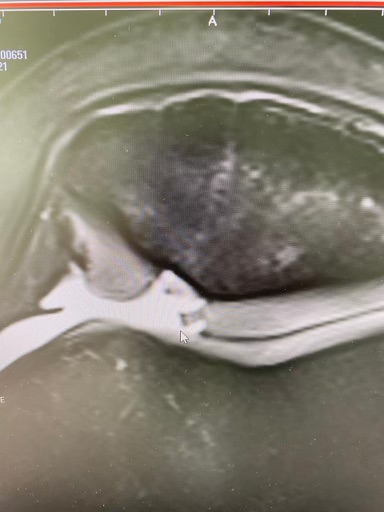

Four weeks ago I hurt my knee while training for the opening World Cup in Solden. Thankfully it was nothing too serious! I did have surgery and have been rehabbing these past 3 weeks.